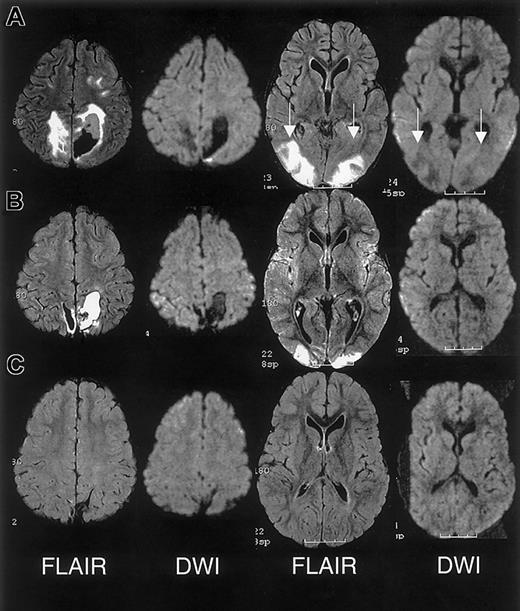

The initial clinical reading of the MRI, 1 day following endotracheal extubation, was bilateral ischemic infarcts and biparietal hemorrhages. The subsequent research reading of the initial MRI and follow-up MRI at 1 month and 15 months following discharge revealed findings consistent with RPLS complicated by hemorrhage; there was no evidence of infarction (Figure 3).

MRI findings for case 3.

(A) Extensive areas of FLAIR T2-weighted signal hyperintensity in the subcortical white matter and overlying gray matter of the posterior, frontal, and occipital lobes. Parenchymal hemorrhage was seen in the high parietal region predominantly on the patients's left. (B-C) Follow-up MRI scan 1 month and 15 months following discharge showed progressive evolution and resolution of the T2 signal hyperintensities with residual encephalomalacia in the left parietal region. These findings were consistent with reversible posterior leukoencephalopathy complicated by hemorrhage; there was no evidence of infarction.